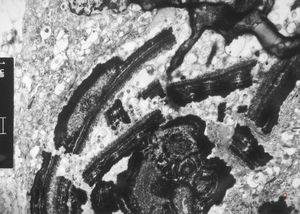

M,66y. | follicular cyst with hyaline Rushton bodies